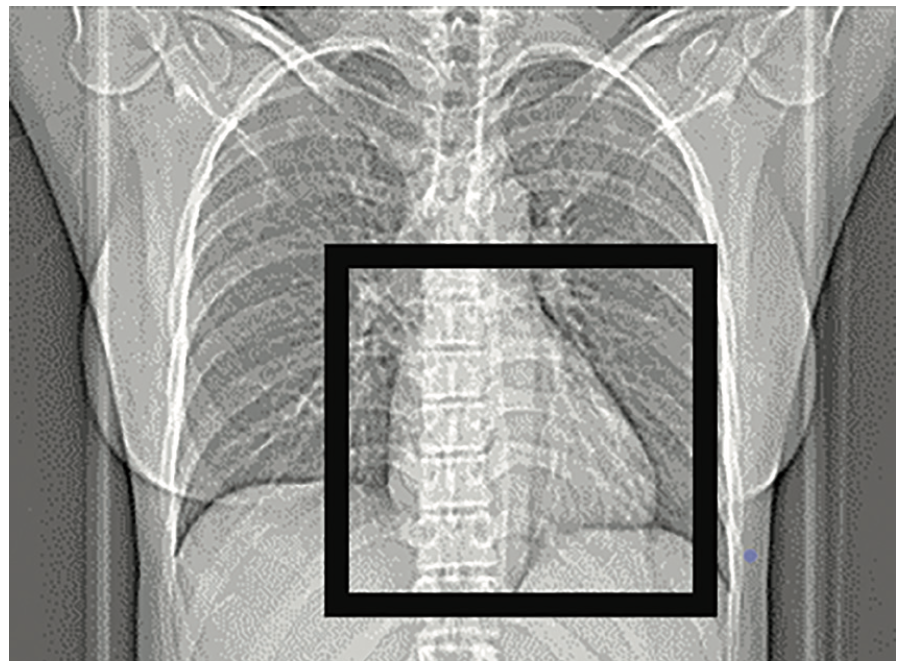

CT calcium scoring is based on a weighted calculation of densities, or calcification, using the Agatston scoring algorithm (Table 1). This algorithm grades plaque burdens on a scoring system of 0 to 400+, with higher scores equaling higher plaque burdens and higher probabilities of CAD. A CT threshold score of 130 Hounsfield units1 (HU) is selected and a coronary score for the left main coronary artery, left anterior descending coronary artery, circumflex coronary artery, and the right coronary artery is obtained. The scanner software identifies calcium in the 4 major coronary arteries and their branches, and assigns a score based on the extent of calcium and density of detects within the coronary arteries (Figure 1).

Procedural preparation involves the placement of 4 electrocardiogram (ECG) leads positioned in the left and right subclavian area, and bilateral leads positioned inferiorly below the ribs. The lead placement minimizes registration artifact on the images. The CT calcium scoring scan utilizes low-dose ionizing radiation, but does not require intravenous contrast or drugs such as beta blockers. These scans are rapidly performed and interpreted.

The main limitations of CT calcium scoring are that it is an out-of-pocket expense unless it is authorized by insurance as part of a CCTA exam. There is also potential for incidental findings due to the display field of view that is used to obtain the scan (Figure 2). Since the display field of view covers the heart and much of the mediastinum, incidental extra-cardiac findings have been reported that may lead to unnecessary follow-up studies and treatments.3